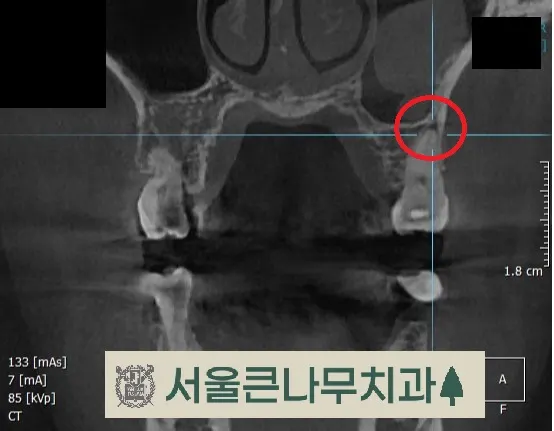

통증이 있는 치아에는 기존에 때웠던 레진 수복물이 있었고 겉보기에는 문제가 없어 보였지만,

자세한 진단을 위해 CBCT 촬영을 해본 결과, 동그라미 친 부위에 뿌리끝 염증이 발견되었습니다.

이전에 치료했던 레진 수복물이 치수에 가까워 신경에 영향을 주었을 것이라고 판단하고 신경치료에 들어갔습니다.